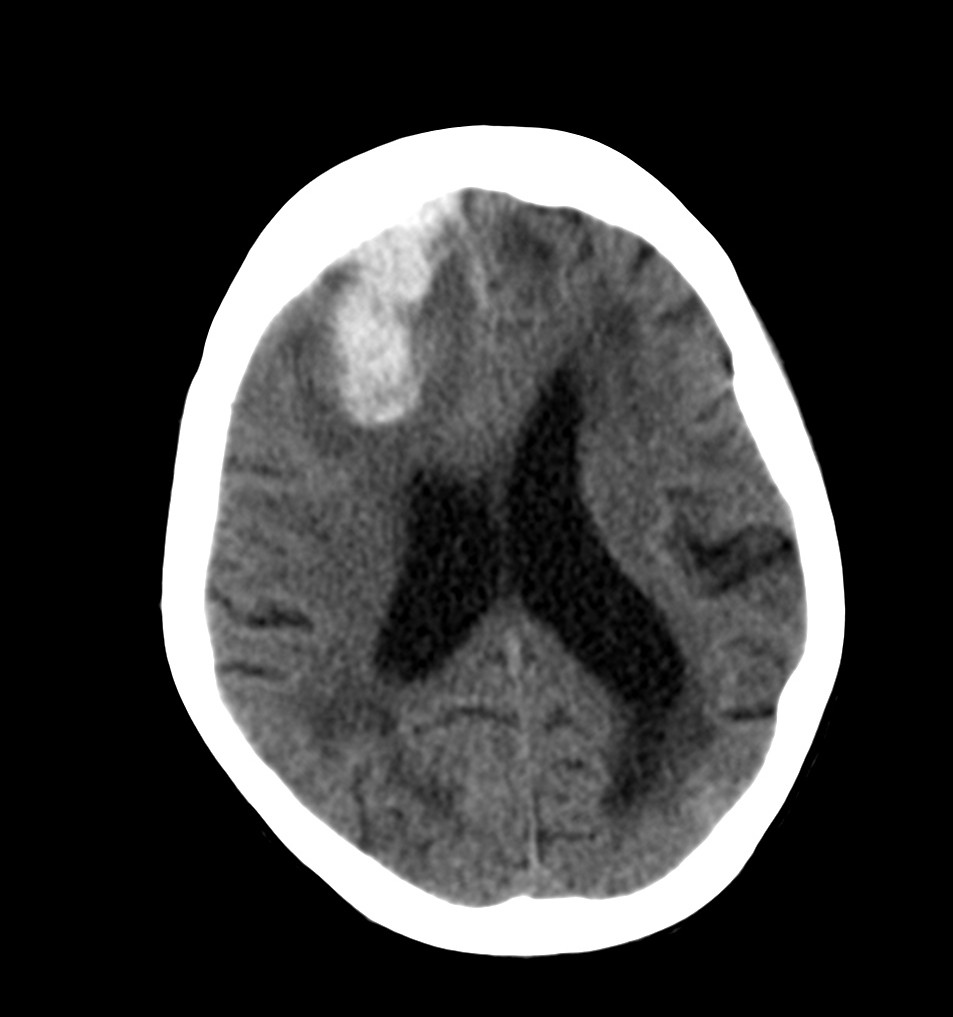

Se realiza un TC de cráneo sin contraste, estos son los hallazgos:

Esta imágen plantea dudas, puede ser una masa o un foco de sangrado, es más, si de esta segunda imagen asumimos que la zona de densidad aumentada corresponde a un sangrado, la pregunta a realizarse ahora es ¿de qué tipo? ¿Es un sangrado intraparenquimatoso, una transformación hemorrágica de un infarto o es otra cosa?

Pues bien, ante los hallazgos descritos, se clarifica que estamos ante un paciente el cual no tiene una masa y que ha sufrido una lesión isquémica hace diez días. Ahora, sobre dicha lesión, tenemos una imagen con un aumento de densidad que sugiere sangrado por una parte y otra hipodensidad en la perifería que correspondería a un edema. Por tanto, descartamos un sangrado intraparenquimatoso de novo. El paciente tiene más de 65 años, no es hipertenso, la imagen del sangrado no es de alta densidad, lo que se opone a una fase aguda o hiperaguda, y tenemos el TC de cráneo previo donde ya se advertía un proceso de tipo isquémico. Por tanto, nos quedan dos opciones, o estamos ante un resangrado de un ACV o estamos ante una Perfusión de lujo.

Consituyen un acontecimiento secundario con extravasación de sangre al tejido infartado. Una embolia obstruye un vaso y produce el consecuente infarto. Posteriormente, la embolia sufre una lisis y se reanuda el flujo sanguíneo y podruce una hemorragia en el territorio infartado. Esto suele producirse sobre todo a las 48 horas del infarto pero puede producirse a la semana o incluso más tiempo después (transformación hemorrágica tardía). La fisiopatología se explica por la creación de ramas colaterales sobre el territorio infartado y la posterior diapedesis o extravasación de los hematíes al territorio infartado a través de dichos vasos colaterales que se formaron. La extravasación de sangre puede ser pequeña, formando petequias que se ven como pequeños núcleos hipercaptantes, o masiva, que corresponde a un hematoma intracraneal. Los infartos hemorrágicos son de morfología serpeante entre las circunvoluciones corticales. Frase literal de Grossman: «Cuando observe esta serpiente, muerda la manzana, escupa el gusano y vea su configuración enrollada. Luego diagnostique de infarto hemorrágico y no de tumor hemorrágico». Los infartos hemorrágicos corticales tienen una evolución similar a las hemorragias intraparenquimatosas, por tanto, en nuestro caso podríamos decir que el infarto parece más evolucionado por la disminución de la intensidad de la sangre extravasada. (Recuerda: La sangre aguda es hiperintensa, la subaguda tardía es isodensa y la crónica es hipodensa).

Vistos los tiempos en los que puede acontecer cada proceso y la atenuación radiológica que se obtiene con la TAC, puede ser dificil distinguir un ACV con transformación hemorrágica, sobre todo si está más evolucionado, de una perfusión de lujo. Necesitaríamos establecer un cronograma radiológico, donde observásemos la evolución de la sangre. En nuestro caso, dadas la evolución y la correlación con la imagen, nos orientaríamos más hacia una perfusión de lujo.